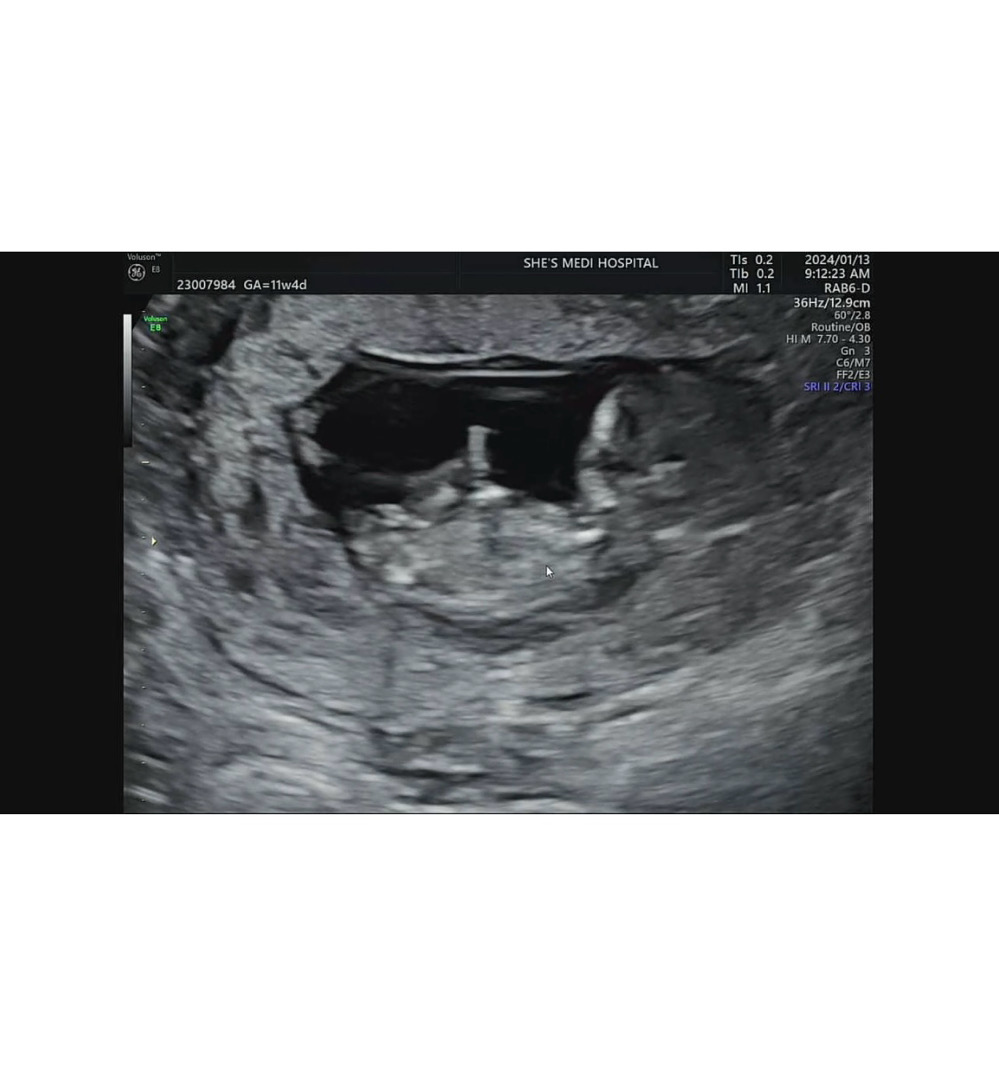

아기집이 작아보이는데

물을 많이 마시면 좋을까요? 의사선생님은 옆으로 보기엔 공간있다고 하시는데 낑겨서 손으로 벽두들기고 발로 팡팡 두들기고 난리더라고욬ㅋㅋ 집아 커져라 커져라 하는것 처럼요 다들 집 크기 어떠셔요?